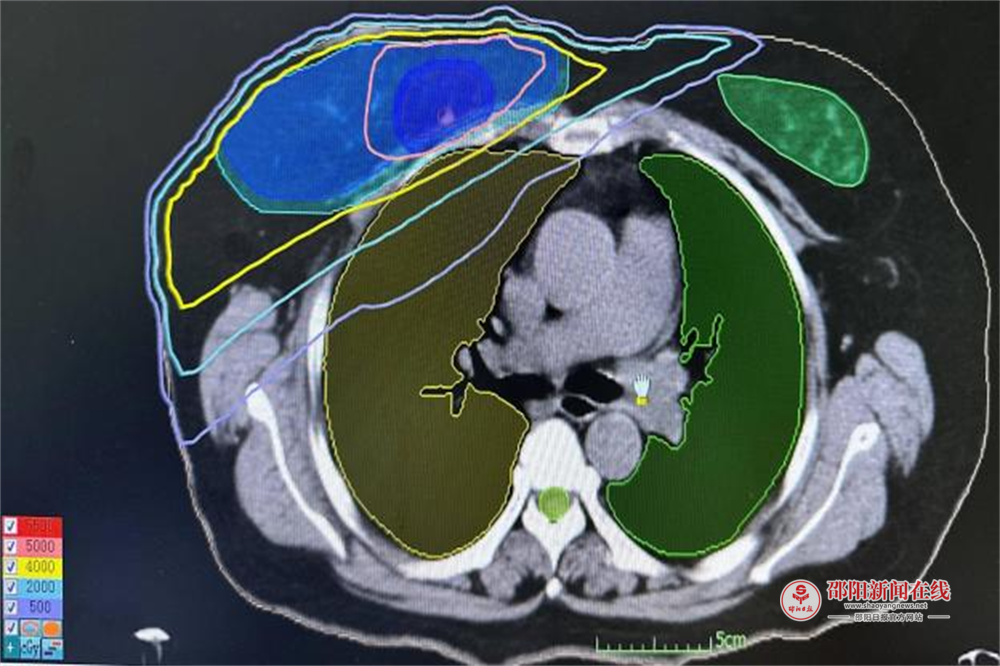

传统乳腺癌保乳术后放疗通常需持续 6-7周,漫长的疗程给患者带来沉重的身心负担。援邵团队创新引入大分割放疗方案,将总疗程压缩至4周,通过优化单次照射剂量、减少治疗次数,在确保疗效的同时,为患者节省时间与经济成本。临床数据显示,采用该技术的患者局部复发率与传统方案持平,且乳房外观保留效果更佳。“既能治好病,又能留住美”——患者的由衷赞誉,正是这项技术价值的最好体现,让更多女性在抗癌路上重拾信心与美丽。